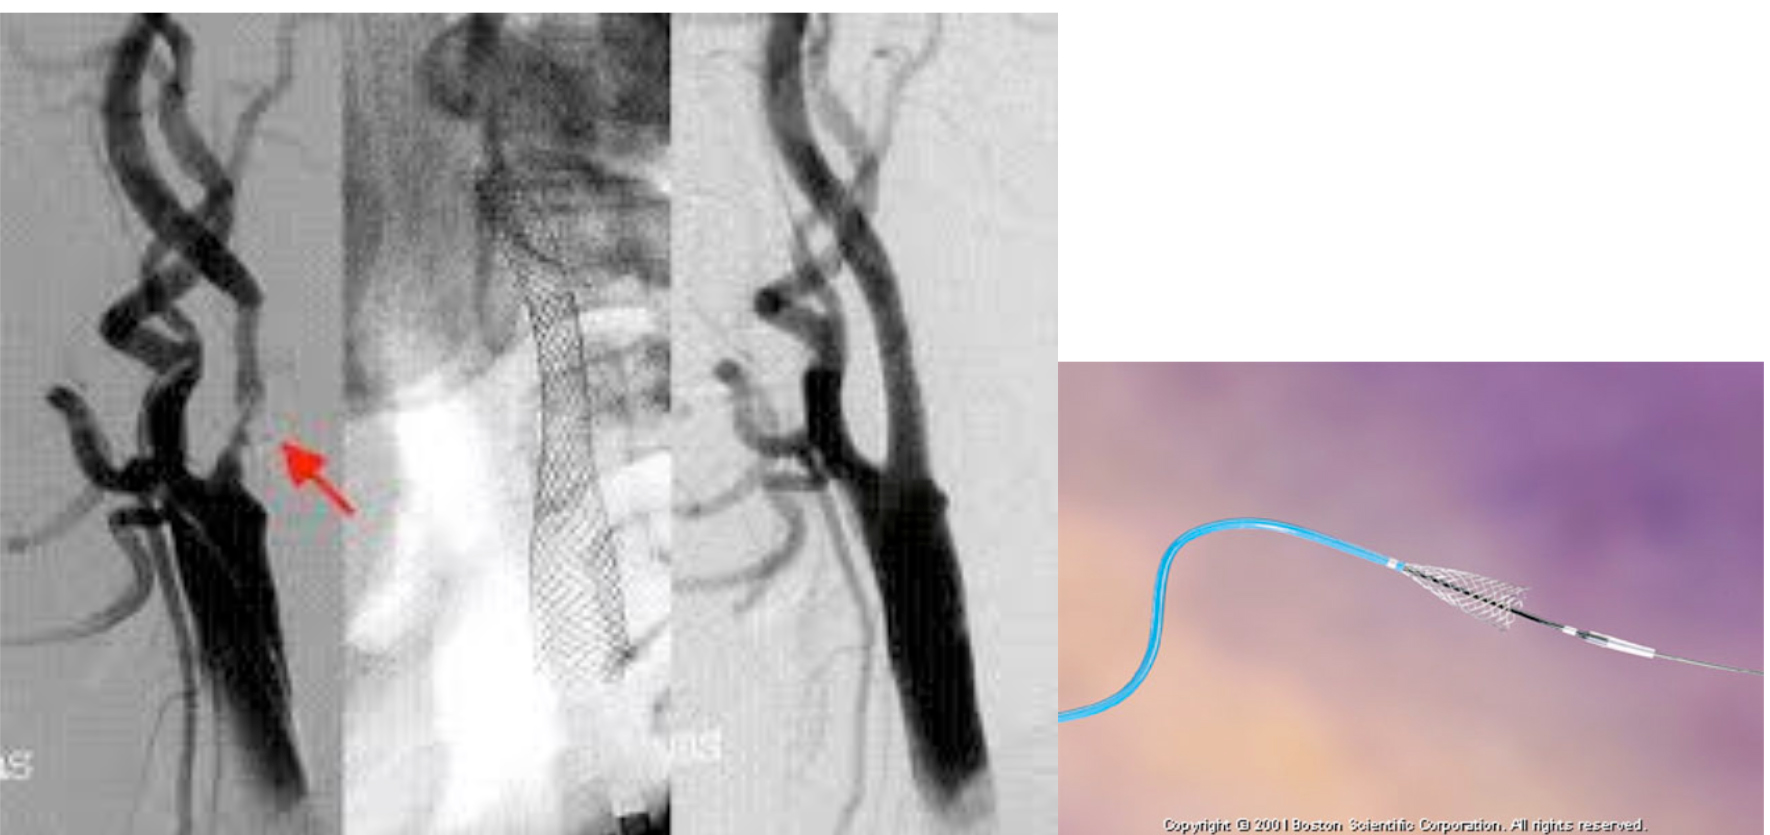

※脳卒中の治療法には大別して2つあり、ひとつは全身麻酔が必要な外科手術、もうひとつは全身麻酔を必要としない局所麻酔下で施行可能な脳血管内治療、すなわちカテーテル手術です。多くの施設ではいずれか一方に偏っていますが、当院は外科手術とカテーテル手術の使い分けができるのが特徴です。 具体的には、脳動脈瘤に対して①開頭クリップング術と②コイル塞栓術があり、頸動脈狭窄症に対し⑴頸動脈内膜剥離術(CEA)と⑵頸動脈ステント留置術(CAS)がありますが、当院では患者さんに応じてそれらを自由に選択し治療できます。

頸動脈ステント留置術(CAS)

2つの治療法には一長一短があり、造影剤を使用するCASは腎不全患者さんには不向きです。 このような患者さんの背景、紹介して頂いた先生方のご希望に沿ってプラークの性状を考慮して、いずれの治療が最適かを選択しています。

治療件数 年間70件以上の頸動脈ステント留置術治療件数は、日本国内においても屈指の多さを誇ります。